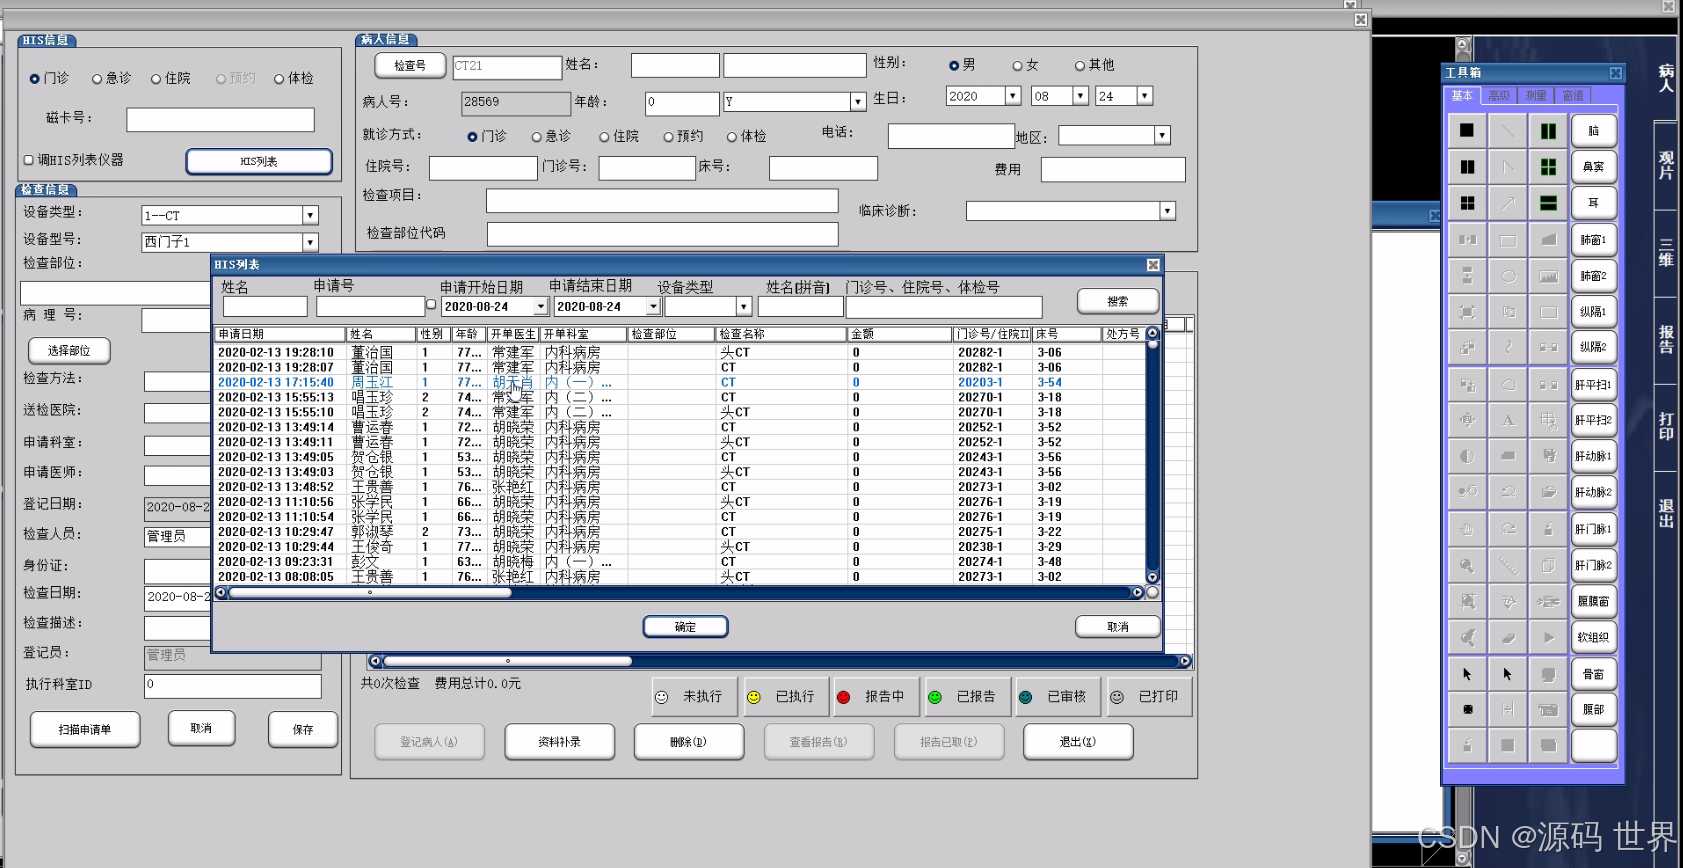

临床工作站用于临床医生快速调阅影像。PACS和HIS融合后,临床医生在HIS工作站上可以调阅影像科室的诊断报告,可以通过临床工作站快速调阅患者影像,进行临床诊断分析。